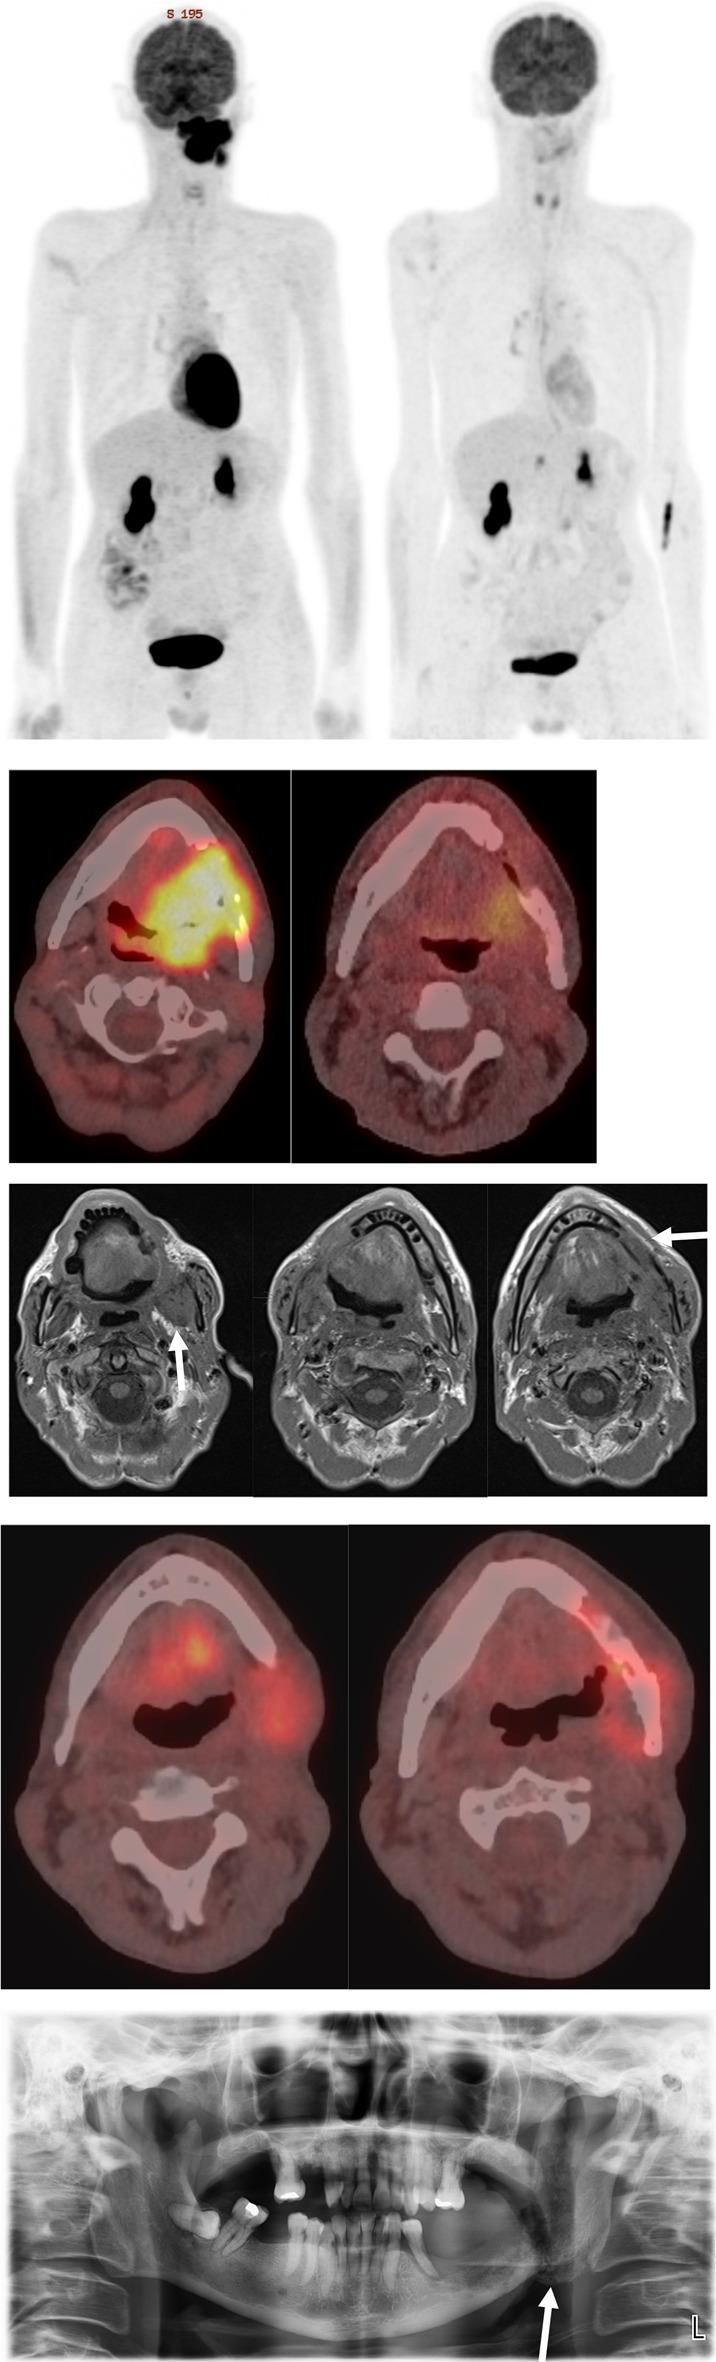

Radiotherapy with or without concurrent chemotherapy is a standard of care treatment for patients with head and neck squamous cell carcinoma (HNSCC). Upon completion, patients are referred for a post-treatment F-FDG PET/CT (Fluorine-18 fluorodeoxyglucose positron emission tomography/computed tomography) scan to help guide ongoing management by assessing for the presence or absence of residual or recurrent disease and differentiating this from post-treatment inflammation. To improve objective reporting of response, we developed the Christie score. The study aims to assess the validity of the Christie score as a response assessment tool in patients with HNSCC and to compare its performance against the widely used Hopkins score.

All newly diagnosed head and neck cancers between July 2018 and July 2020 were retrospectively reviewed. In total, 291 patients (224 men and 67 women) were included in the study. Patients with squamous cell carcinoma of the nasopharynx, oropharynx or oral cavity, hypopharynx or larynx were included. All other cell lineages or anatomical locations were excluded. Hopkins and Christie scores were applied to post-treatment PET/CT, and sensitivity, specificity, positive predictive value, negative predictive value, and likelihood ratio assessed for each score. Fisher's exact tests and receiver-operating characteristic (ROC) curves were used to determine the ability of the Hopkins and Christie scores to differentiate residual or recurrent disease from treatment response. p values < 0.05 were considered to indicate statistical significance.

39 patients (13%) were confirmed to have residual or recurrent disease. This was significantly more likely in patients with positive Hopkins (p < 0.0001) and Christie (p < 0.0001) scores. The Christie score has a higher sensitivity (92% vs. 85%) and negative predictive value (99% vs. 97%) compared to Hopkins, though the differences were not statistically significant. Comparison of the ROC curves for the Hopkins and Christie score revealed no significant difference between the two scores' ability to discriminate patients with residual or recurrent disease from cases where disease is absent (p = 0.382). 'Subjectivity rates' of the 291 patients are as follows. Six patients (2.1%; 95% CI 0.76-4.5%) were assigned borderline scores on the Hopkins criteria, compared to only a single patient (0.3%; 95% CI 0-1.9%) on the Christie criteria. The 'subjectivity rate' difference is 0.017 (95% CI - 0.06 to 3.5%; p = 0.06) and the ratio is 6.0 (95% CI 0.73-276; p = 0.07).

Our study identifies three clear results: (a) the Christie score is an excellent treatment follow-up assessment tool; (b) it is comparable with current gold standard methodology showing no statistically significant differences in performance when compared with the Hopkins score; and (c) there was a lower rate of observer variation when using the Christie score, which is trending towards significance.